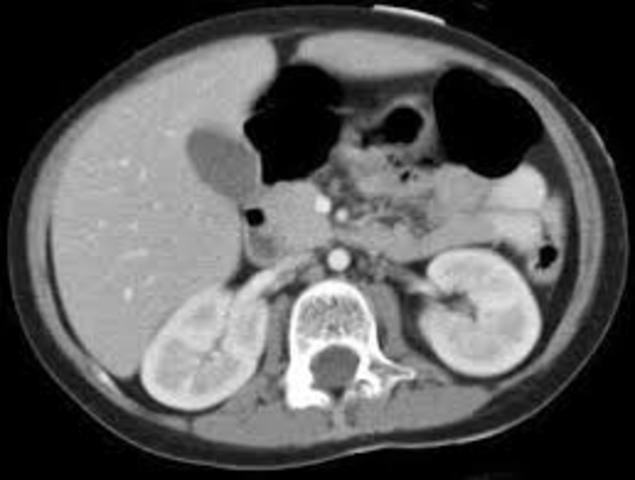

aparecieron en 1974 y el numero de detectores aumento a

30 y el tiempo de adquisición de datos disminuyo a 20 seg. La traslación era más rápida y se

utilizo para estudiar tórax y abdomen.